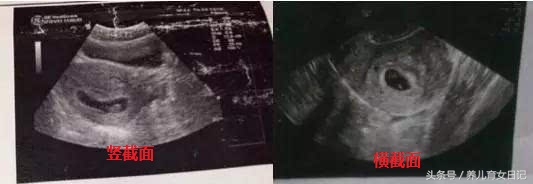

首先仅限8周之前的B超单,40多天是最合适的,然后就是要有3个数据的,如果没有3个数据的,一律不能判断,因为孕囊都是圆柱状的,可是B超师做B超的时候,截面会截取的方位不一样,有的横截面,有的截取竖截面,所以,看图片是长的还是圆的,不能判断男女。

很多妈妈的B超单上只有两个数据,比如4.0cm*2.6cm,这只是横截面的数据,不能用来看男女,很多妈妈看错就是这个原因。只有3个数的数据才能看,比如4.0cm*3.8cm*2.6cm。当两个数据差不多,第三个数据比前两个小近一倍,那一般就是儿子,如果成递减数据就可能是女儿。

比如B超单上是4.0cm*4.0cm*2.0cm,那肯定是男孩,但是如果B超师横截面时,孕囊就成了4.0cm*4.0cm的两个数据,看上去就是圆的了,然后造成了,孕囊是圆的,结果怎么生出了儿子,貌似不准的误导。